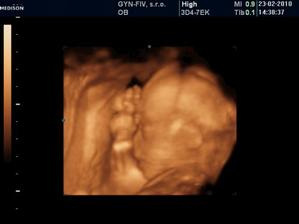

Ako rýchlo rastieme v brušinku 🙂

tatianka ďakujeme veľmi pekne 🙂 aj my sa z nich vytešujeme, kým je malinká v brušku a nevidím ju naživo